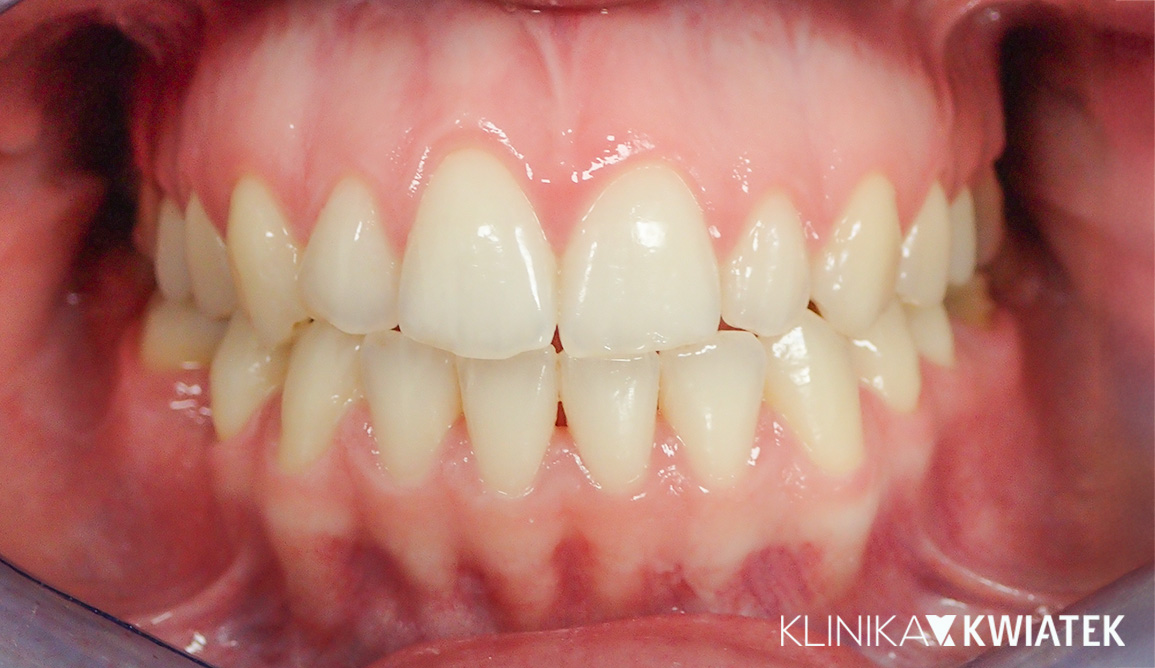

Kompleksowa transformacja uśmiechu po leczeniu ortodontycznym

Pacjentka zgłosiła się do kliniki po zakończeniu leczenia ortodontycznego nakładkami w innym gabinecie, w celu odbudowy brakującego zęba trzonowego. Po szczegółowej diagnostyce zaplanowano leczenie implantologiczne, protetyczne oraz periodontologiczne. Dzięki precyzyjnej pracy zespołu specjalistów uzyskano pełną odbudowę estetyki i funkcji – naturalny, harmonijny uśmiech oraz zdrowe, stabilne przyzębie.